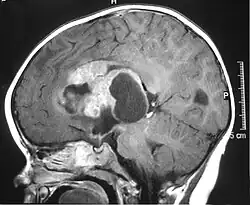

| MRI of an AT/RT | |

- Magnetic resonance imaging (MRI) of the brain and spine

The initial diagnosis of a tumor is made with a radiographic study (MRI[28] or CT-). If CT was performed first, an MRI is usually performed as the images are often more detailed and may reveal previously undetected metastatic tumors in other locations of the brain. In addition, an MRI of the spine is usually performed. The AT/RT tumor often spreads to the spine. AT/RT is difficult to diagnose only from radiographic study; usually, a pathologist must perform a cytological or genetic analysis.

Appearance on radiologic exam

AT/RTs can occur at any sites within the CNS; however, about 60% are located in the posterior fossa or cerebellar area. The ASCO study showed 52% posterior fossa; 39% sPNET; 5% pineal; 2% spinal, and 2% multifocal.[3]

The tumors' appearance on CT and MRI are not specific, tending towards large size, calcifications, necrosis (tissue death), and hemorrhage (bleeding). Radiological studies alone cannot identify AT/RT; a pathologist almost always has to evaluate a brain tissue sample.

The increased cellularity of the tumor may make the appearance on an uncontrasted CT to have increased attenuation. Solid parts of the tumor often enhance with contrast MRI finding on T1 and T2 weighted images are variable. Precontrast T2 weighted images may show an isosignal or slightly hypersignal. Solid components of the tumor may enhance with contrast, but not always. MRI studies appear to be more able to pick up metastatic foci in other intracranial locations, as well as intraspinal locations.

Preoperative and follow-up studies are needed to detect metastatic disease.